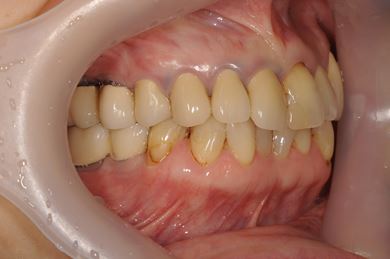

インプラントの症例写真 IMPLANT

骨再生スピードインプラント治療+セラミック治療

| 主訴 | 左上の歯に以前から歯周病があり、多少のぐらつきがあったが、ここにきていよいよ限界になりました。食事に影響があるので、インプラントを視野に、とりあえずは抜歯をと思っています。 | ||||||||||||||||||||||||||||||||

| 治療方針 | サイナスリフトにて上顎洞を拳上し、インプラント治療を可能にする。抜歯と同時にインプラント埋入を行い、治療期間を短縮する。 | ||||||||||||||||||||||||||||||||